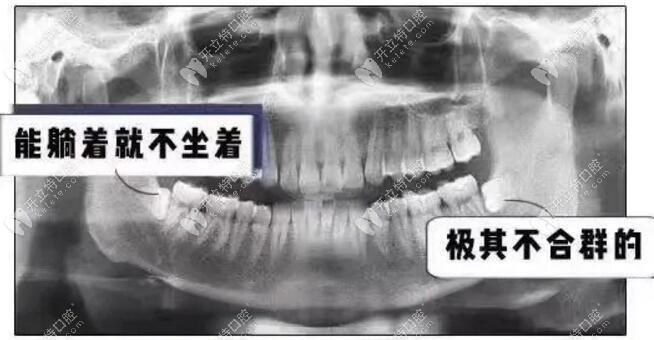

▼長(zhǎng)得很對(duì)稱,4顆智齒清潔不到▼

長(zhǎng)得很對(duì)稱,4顆智齒清潔不到